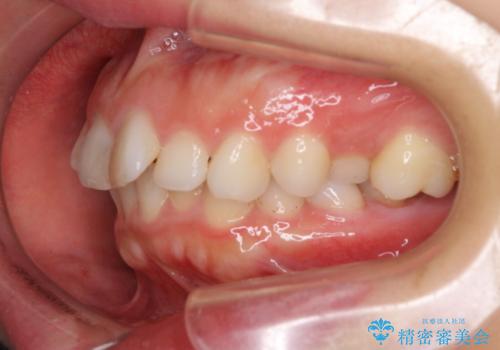

奥歯の咬み合わせ改善には1年ほどの期間と処置中の噛みにくさを強いることとなりましたが、抜歯後はスムーズに治療を完了させることができました。

歯ぎしりの際に奥歯が干渉していた咬み合わせも理想的な状態に改善できました。